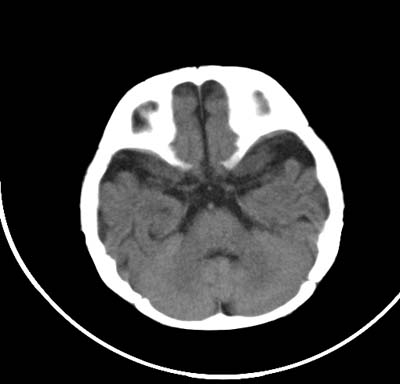

以下是引用影象小泰斗在2008-6-30 15:57:00的发言:[br]双侧额、颞部蛛网膜下腔增宽,纵裂加深, 支持外部性脑积水![br] 双侧基底节点状钙化!

以下是引用jiangjing在2008-6-30 17:19:00的发言:[br]双侧额、颞部蛛网膜下腔增宽,纵裂加深, 支持外部性脑积水![br] 双侧基底节点状钙化![宫内感染形成可能]